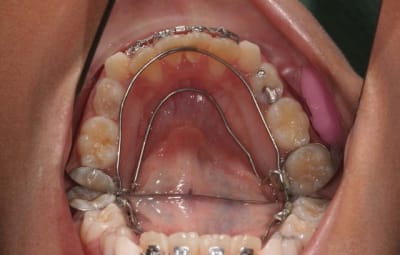

Img 1 xacnga - Eugenol

Img 2 siytdm - Eugenol

Img 3 ituagt - Eugenol

Img 4 r3tw6u - Eugenol

Img 5 z8ak0k - Eugenol

plus ce surcontour sera important, plus la plaque se déposera en dessous et sera difficile à éliminer. ici, ce qui me plait est que le surcontour est très fin, mais il existe quand mm. et demande un bon contrôle de plaque.

dans le cas présenté, lorsque le composite de recouvrement s’usera, ce sera du métal (or) qui sera mis à nu. ceux qui ont vu des stéllites en or dans une bouche comprendront l’avantage sur une fibre en partie effilochée.

et ce qui ne gâte rien, je le trouve très facile à mettre en place, plus facile qu’un ruban, et aussi esthétique

3°) phase

contention

@+ Bjc